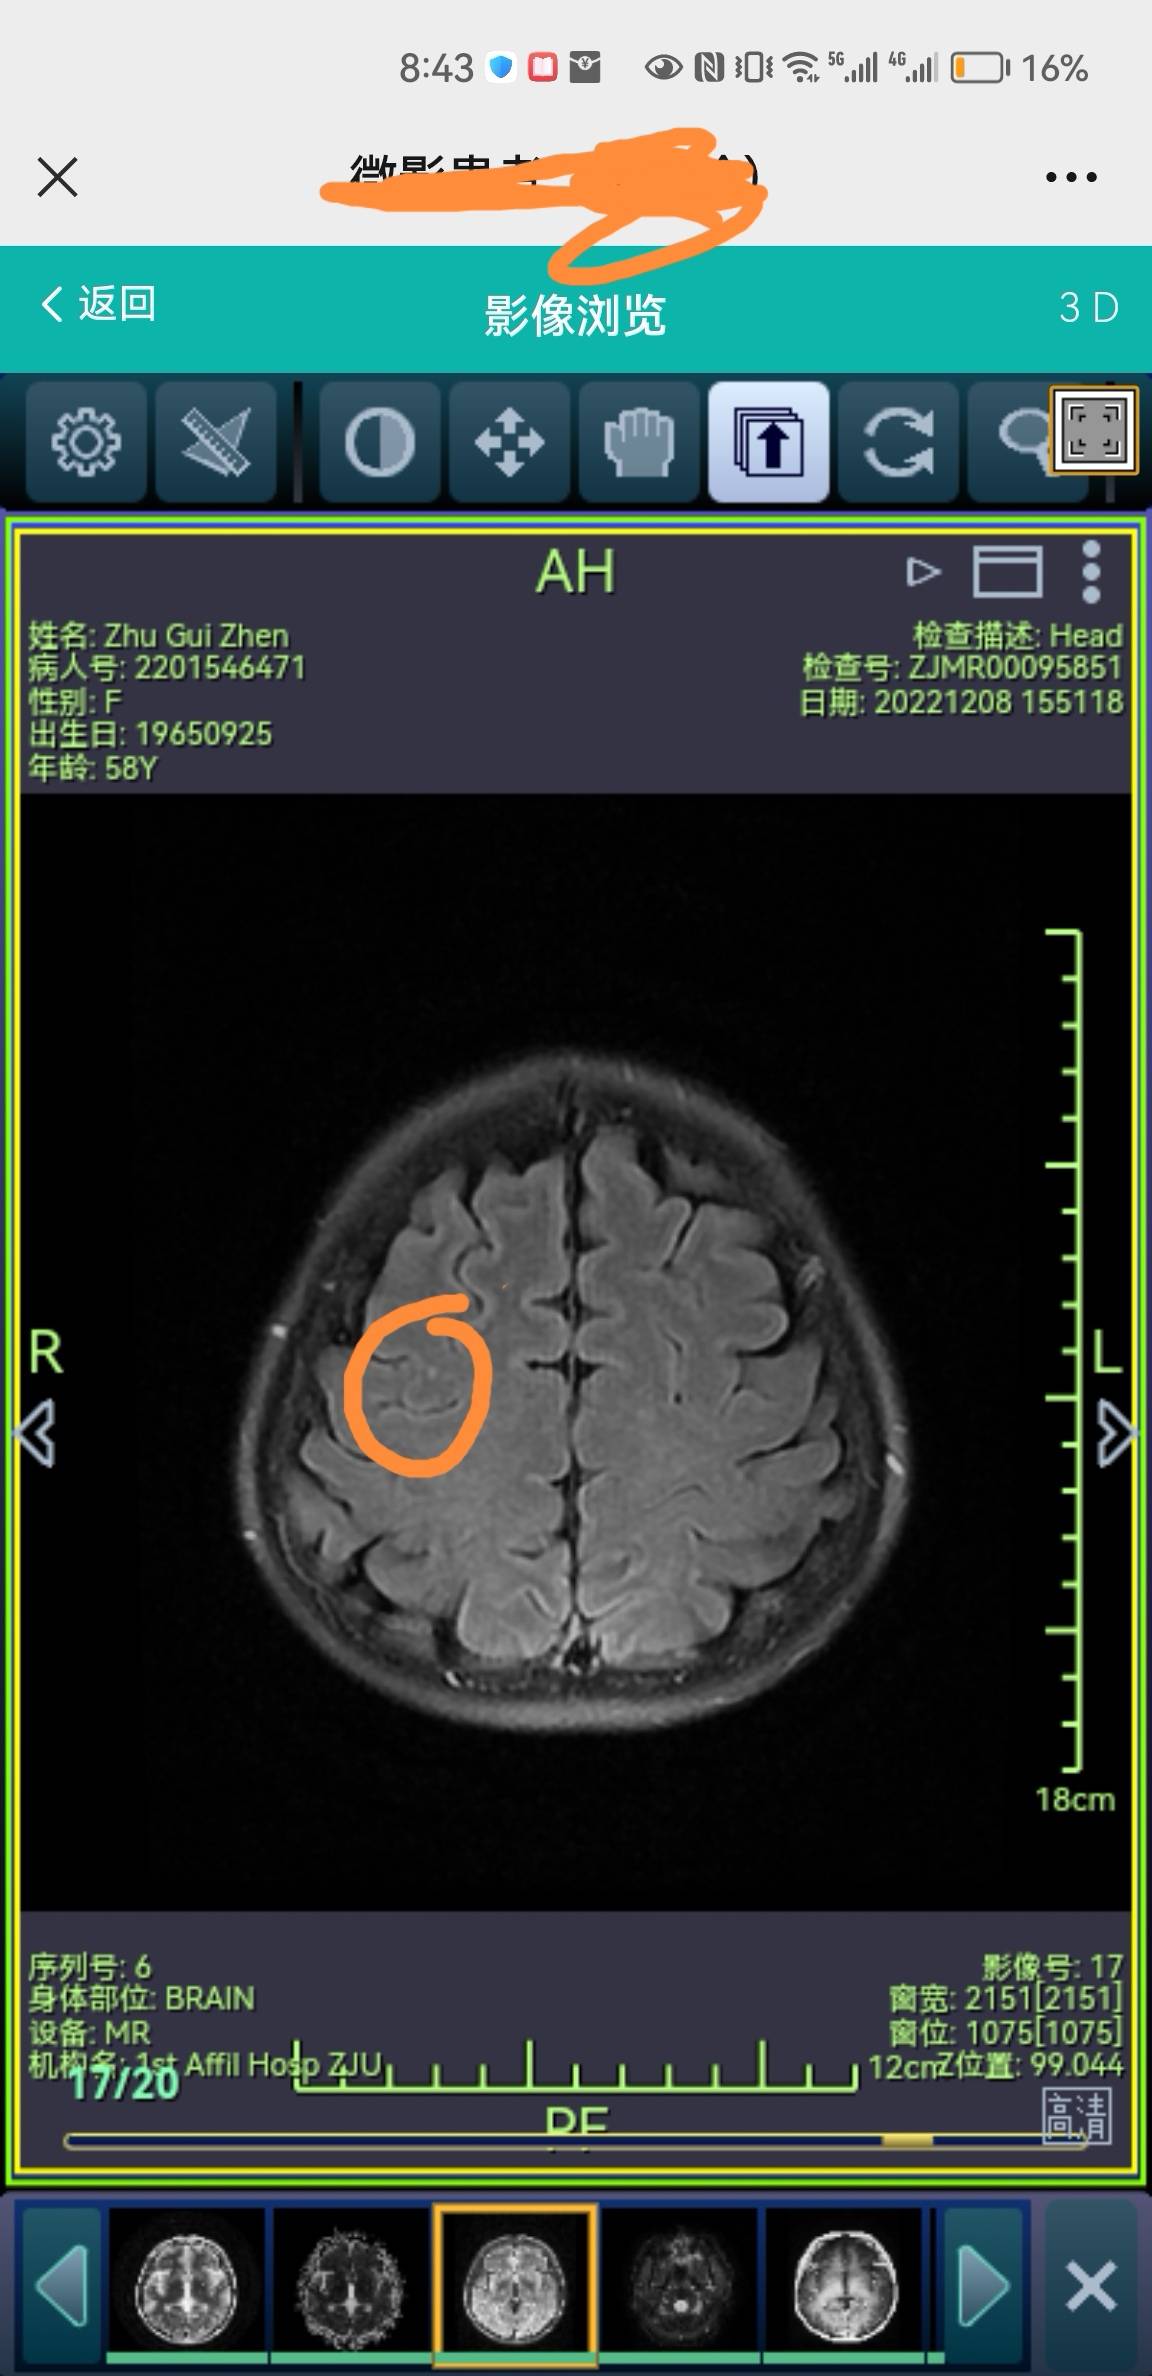

着急解决我的疑惑,我打开了我妈上次复查的脑核磁,发现应该是杭州的医生把病灶漏掉了,我在片子上找到了,但是这次跟上次有什么变化,还得明天听医生的结论,果然,复查最好在同一个医院,方便对比片子,不然很容易漏掉微小的病灶,上次白高兴一场了,还没敢和我妈说,自从脑转移后,她只要头疼就怀疑这个问题,不想让她心理负担太重,但是明天也是瞒不住的,今晚就先让她睡个好觉吧。